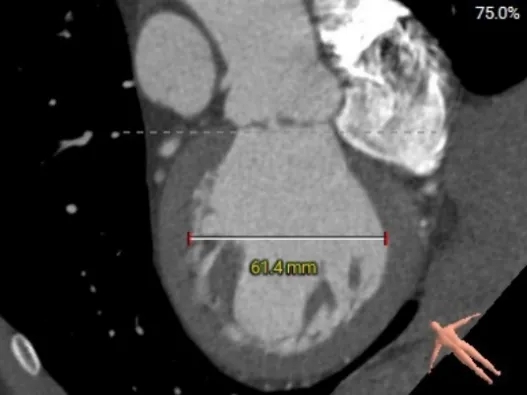

术前CT分析

患者为Type-1型二叶式主动脉瓣,无钙化

收缩期主动脉瓣环周长径27.8mm

收缩期LVOT周长径28.2mm

Type-1型二叶式主动脉瓣,R-L融合

瓣叶增厚,瓣上结构较大,锚定能力较低

STJ周长径29.6mm

升主动脉周长径31.9mm

瓣环水平夹角51°

主动脉弓部角度98°

根部结构HU850下无钙化

左室舒末内径增宽

外周入路条件尚可